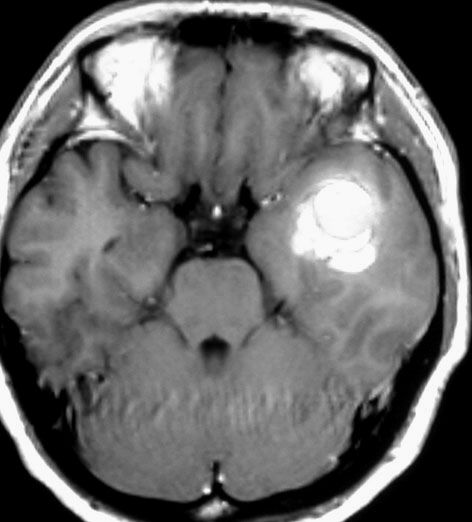

左上のT2*でみられるように多発性海綿状血管腫の成人男性に発生した中脳海綿状血管腫です。複視と歩行失調で発症して,数回の脳幹部出血を繰り返し,水頭症になったために第3脳室開窓術がなされました。それでも出血は止まらず、両側の動眼神経麻痺による両側眼瞼下垂,歩行失調,嚥下障害などさまざまな中脳症状が進行しました。

しかたがないので手術で摘出しました。なんとか眼瞼が持ち上がるようになり歩行も可能で嚥下もできます。幸いだったのは感覚路(脊髄視床路)の障害による体性疼痛が生じなかったことです。

手術は経テント法 OTA という手法でした(クリックと手技が書いてあります)

片方の下丘の損傷だけでは神経脱落症状が出ないので,中脳内部の腫瘍を摘出するには下丘という狭い場所を切開して入りますが,この患者さんは左上丘も出血のために破壊されていて,間口が広かったといえます。でもこの手術は難しすぎるので決して積極的にはしません。